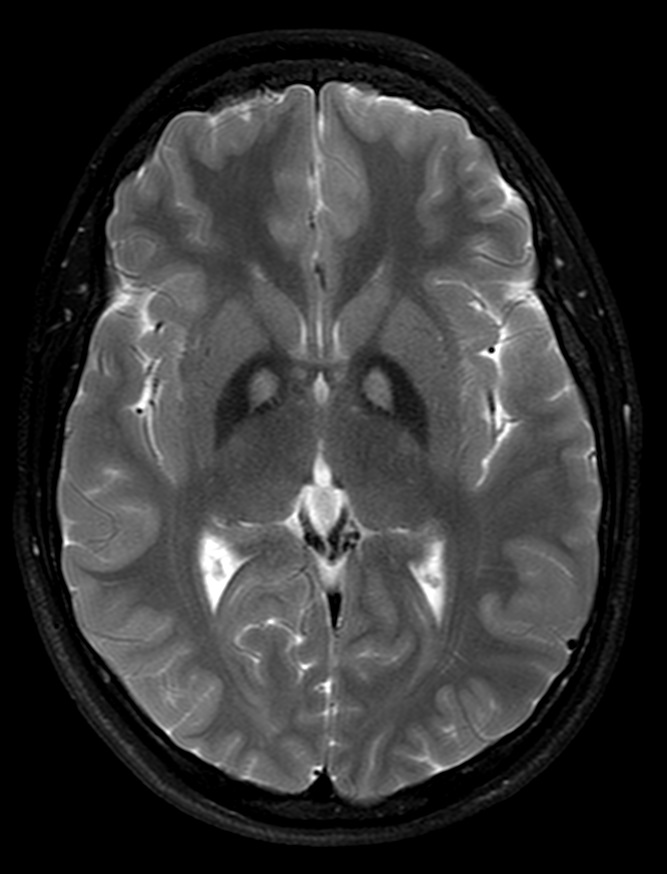

Ante el diagnóstico del cuadro se realiza Resonancia Magnética cerebral a su hermano gemelo, con sintomatología más leve (alteración conductual aislada, mayores capacidades cognitivas, ausencia de clínica extrapiramidal), obteniendo la misma imagen característica de ojos de tigre. Se realiza estudio genético dirigido a mutaciones en gen PKAN2, confirmándose la misma mutación.